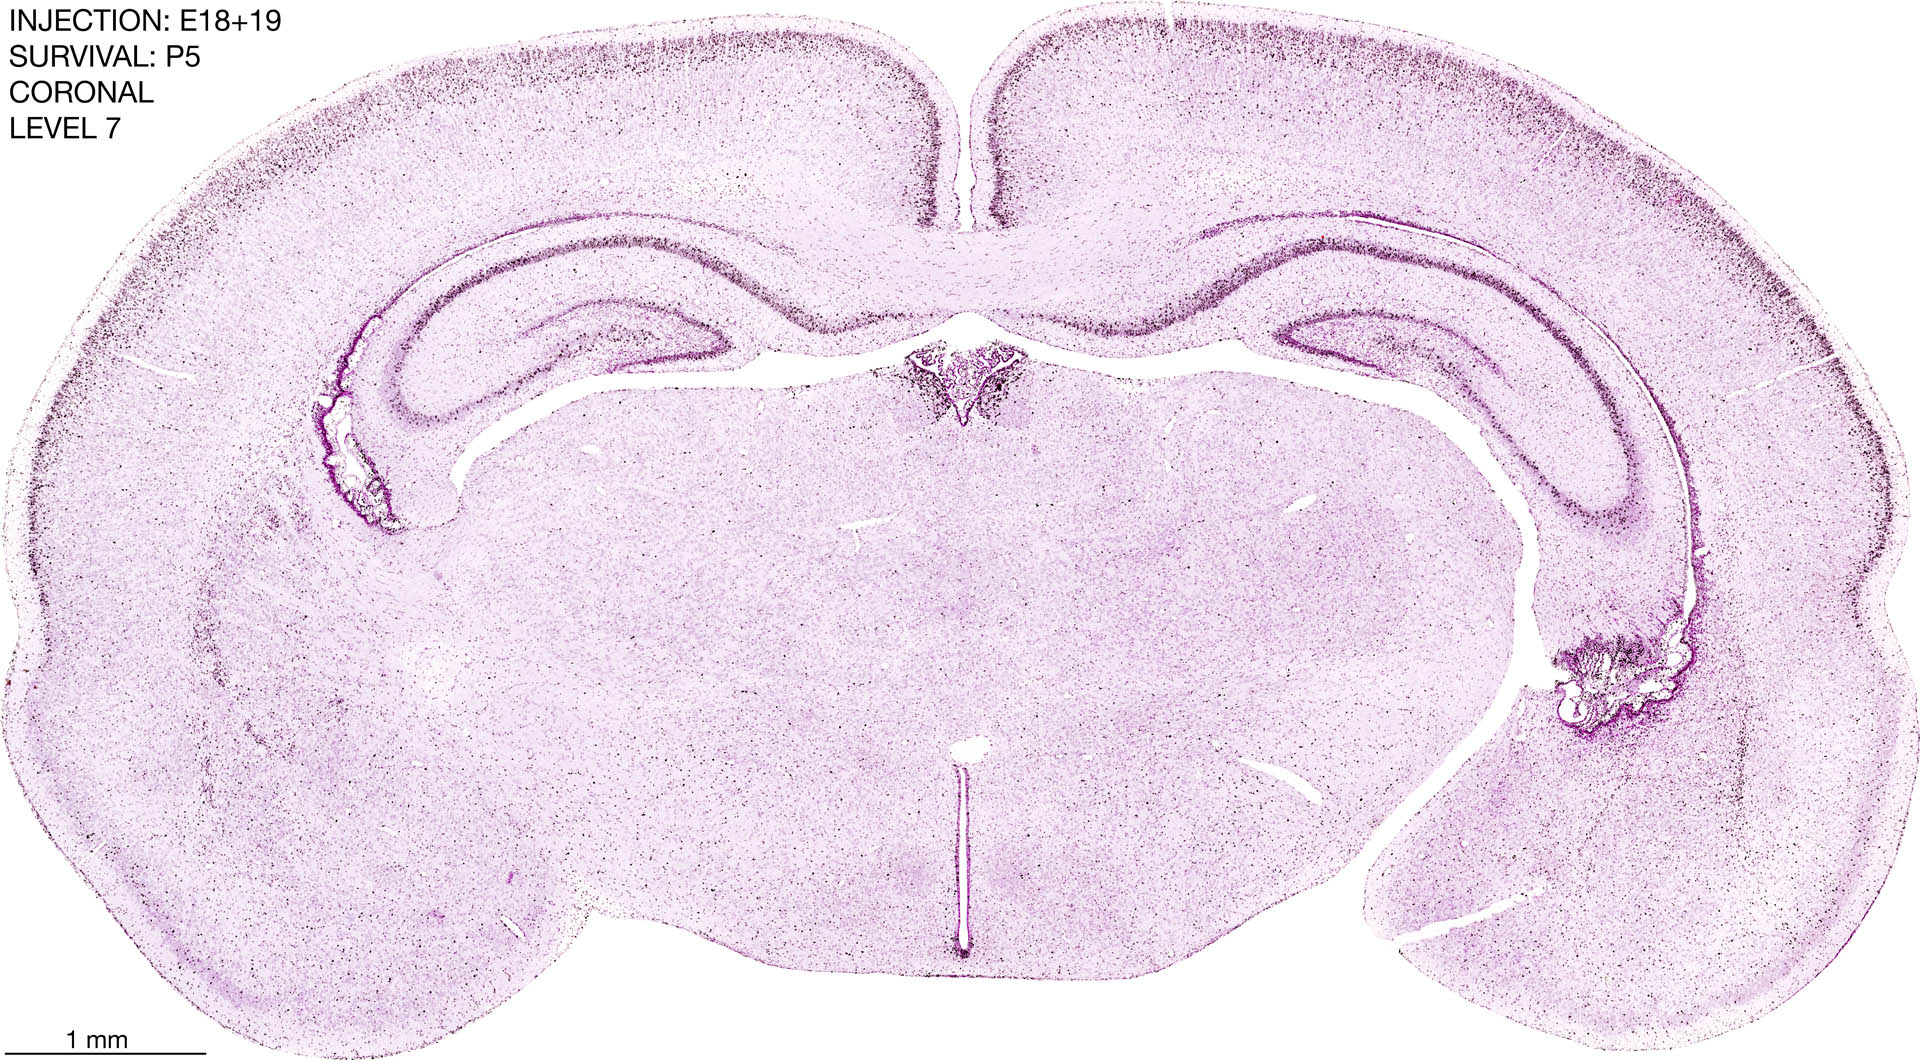

The images below are from the brain of a rat that was exposed to tritiated thymidine on E18+19 and survived to P5. Download: Large | High Res Download: Large | High Res Download: Large | High Res Download: Large | High Res Download: Large | High Res Download: Large | High Res Download: Large | High Res Download: Large | High Res Download: Large | High Res Download: Large | High Res Download: Large | High Res Download: Large | High Res Download: Large | High Res Download: Large | High Res Download: Large | High Res Download: Large | High Res Download: Large | High Res Download: Large | High Res Download: Large | High Res Download: Large | High Res Download: Large | High Res Download: Large | High Res Download: Large | High Res Download: Large | High Res